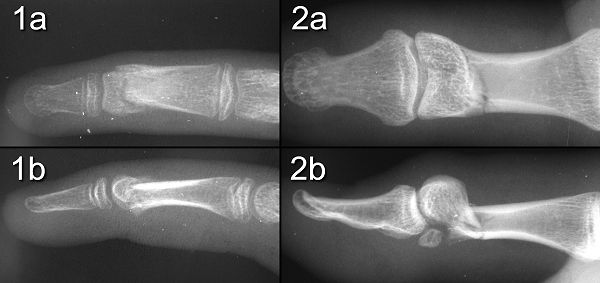

Figure Legend: Phalangeal neck fractures

are sometimes referred to as "hangman's fracture", either because the break

is through the "neck" of the bone, or more importantly because the PA x-ray

may be deceptively normal (1a,2a), despite extension rotation of the distal

fragment, as in these cases, rotated 30 (1) and 70 degrees (2). Ninety

degree rotation may occur with little change on the PA view. Such

fractures are prone to avascular necrosis of the distal part, even more

so following later attempts at corrective osteotomy.